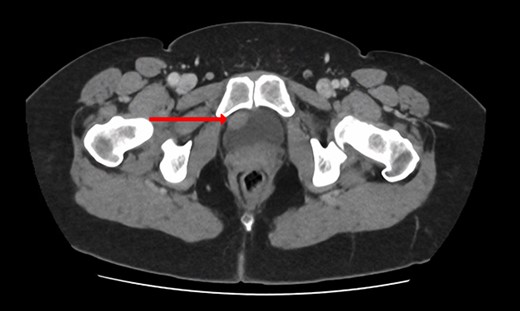

Blood tests included full blood count revealing all parameters within normal limits, eGFR >90 ml/min/1.73m2, Creatinine 64 umol/L and urea 4.5 mmol/L. Urine cultures were negative for infection. Ultrasound revealed a normal-appearing urinary tract, with both kidneys normal in size, shape and echopattern. Flexible cystoscopy revealed only a cystic lesion near the bladder dome which instigated further investigation; subsequent contrast-enhanced Computerized Tomography (CT) abdomen-pelvis scan showed a potential urachal remnant consistent with the flexible cystoscopy finding. In addition, a 1.5-cm-soft tissue structure was identified near the bladder neck which was not clearly seen initially at cystoscopy (Figs 1 and 2).

CT urogram (axial view) revealing a 1.5 cm thickening at the level of the right lateral bladder neck, and a 1-cm-soft tissue thickening at the bladder dome.